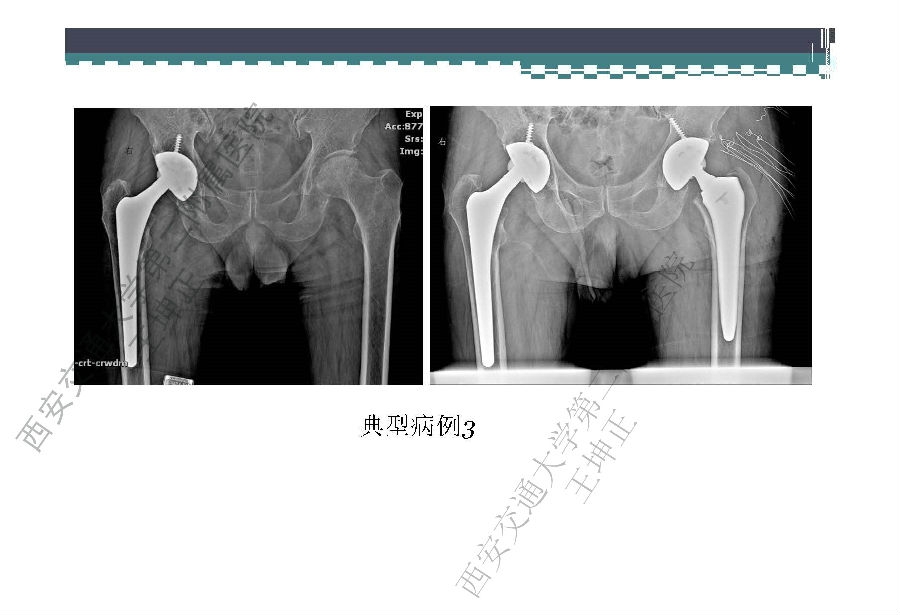

对于关节外科而言快速康复实际上是以病人加速舒适康复为目的,加强围术期的综合管理,包括疼痛和睡眠管理、血栓预防管理、感染预防管理、围术期血液管理,减少放置引流管、尿管、减少止血带应用,减少术后恶心呕吐,尽早进食,尽早康复等,逐步达到无血、无痛、无栓、无感、无肿、无管、无吐、无带等优良效果。为此,小编特邀王坤正教授等多位关节外科的专家参与撰写快速康复外科在关节外科的应用的主题文章,共话“人工关节置换快速康复”新理念,探讨建立符合我国特色的关节置换围手术期管理与快速康复体系,促进我国关节外科技术整体发展与提高。